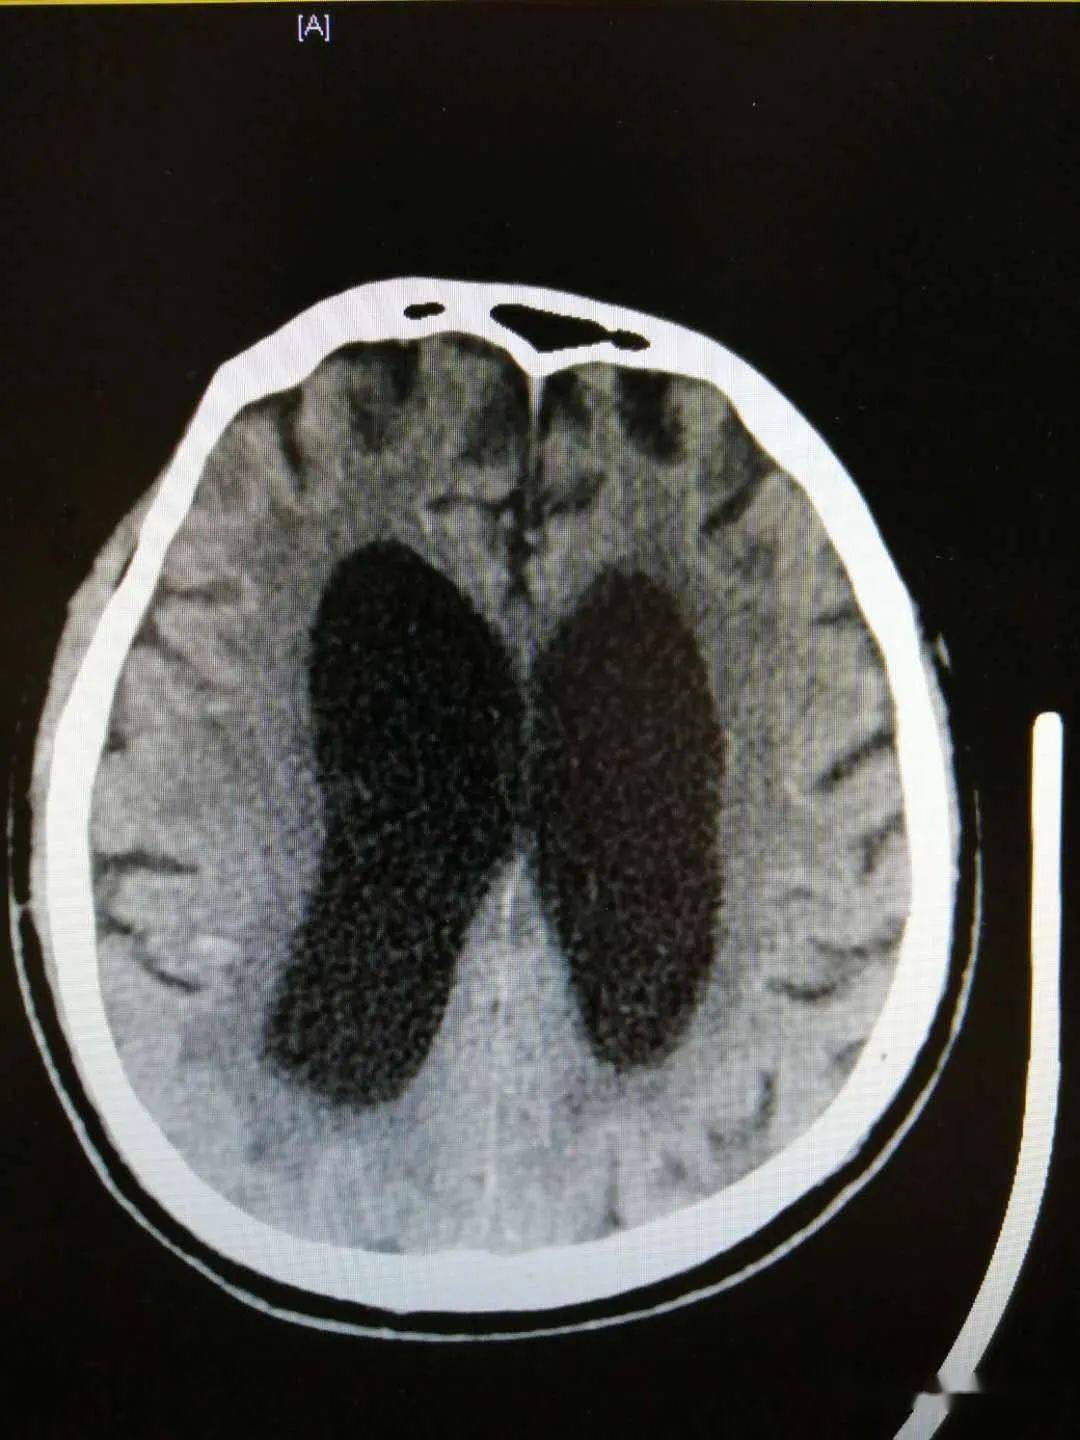

步态不稳反应迟钝老年痴呆不一定当心脑积水

图片尺寸1080x1440